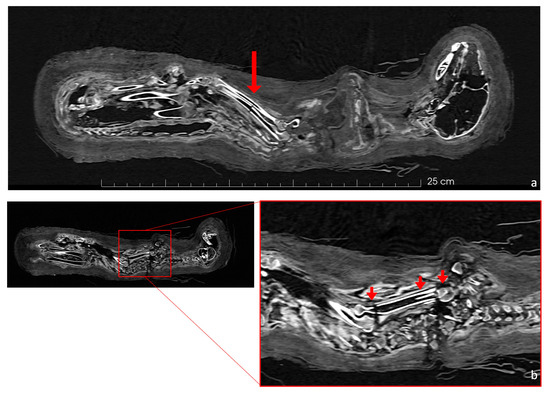

Several significant fractures were present in the postcranial skeleton. The forelimbs were damaged; the left humerus had a dislocation in the proximal epiphysis, the left ulna and radius showed a break in the middle of the diaphysis (Figure 6a), and the right humerus had three separate fractures: a dislocation in the proximal diaphysis, a detachment of a shrapnel fragment that moved into the medullary cavity, and a separation of the distal part of the bone (Figure 6b).

Figure 6.

Coronal view of specific fractures in the cat skeleton. (a) The red arrow indicates the fractures of the left ulna and left radius (left side). (b) Three fractures of the humerus are marked by red arrows: (from left to right) a fracture of the distal epiphysis; the presence of a shrapnel fragment in the humerus; and a 90-degree dislocation and rotation of the proximal head.

Most of the postcranial elements have evident fractures, such as those indicated in Figure 4. The breaks on the limb bones seem to have occurred post-mortem, unlike the fractures on the skull and vertebrae. For example, the proximal part of the humerus is separated and rotated by 90 degrees in relation to the bone’s diaphysis (Figure 6b). The manipulation, embalming process, and positioning of the skeleton may have compromised the structural integrity of the bones, as did its burial and subsequent transport, since there is no evidence for bone repair/growth.